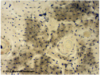

Sublingual Gland

* Mucous acini (pale in appearance)(PAS+)

* Flattened nuclei at basal poles of cells.

* Myoepithelial cells surround acini.

Sublingual Gland

* Mucous acini (pale in appearance)(PAS+)

* Flattened nuclei at basal poles of cells.

* Myoepithelial cells surround acini.